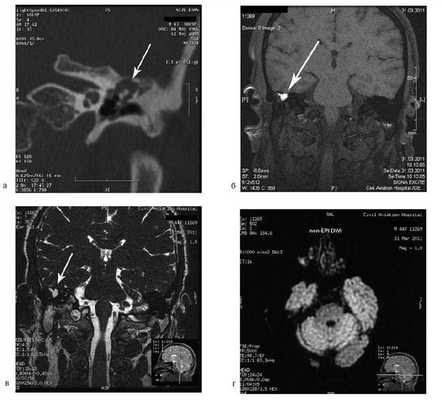

Больная Ф., 30 лет, обратилась с жалобами на головокружение, снижение слуха на правое ухо, слизистое отделяемое из правого уха. Болеет в течение 6 лет, лечилась консервативно. При отомикроскопии визуализируется перфорация в верхнем отделе барабанной перепонки.

Пациентке была выполнена МРТ основания черепа по описанной методике (рис. 1). Рисунок 1. МРТ основания черепа больной Ф. с хроническим правосторонним гнойным средним отитом. Фистула лабиринта. Холестеатома. а — исследование в режиме Т1; б — в режиме Т2; в — в режиме non-EPI DWI.

В режиме Т1 справа определяется образование с низкой интенсивностью сигнала, а в режиме Т2 и non-EPI DWI — образование с гиперинтенсивным сигналом. Диагноз: хронический правосторонний гнойный средний отит; холестеатома; фистула лабиринта. Пациентка была подвергнута санирующей операции на правом ухе с тимпанопластикой и облитерацией паратимпанальных пространств. Были выявлены холестеатома, заполняющая аттик, адитус, антрум, деструкция цепи слуховых косточек, фистула латерального полукружного канала. Послеоперационный период протекал без особенностей, на 15-е сутки была удалена гемостатическая губка и силиконовая выстилка. При контрольном осмотре ухо сухое, отмечает улучшение слуха, головокружения нет. Через 12 мес проведено повторное МРТ-исследование. Признаков холестеатомы не обнаружено. Получен хороший функциональный результат — ухо толерантно к воде, самоочищается.

Больная У., 25 лет, обратилась с жалобами на снижение слуха на правое ухо, периодические выделения из правого уха. 18 лет назад была выполнена радикальная операция по поводу острого мастоидита, острого гнойного среднего отита справа. После операции развился парез лицевого нерва. В связи с продолжающимися обострениями через 8 лет была выполнена повторная операция с тимпанопластикой и мастоидопластикой. Частота обострений снизилась, но периодические выделения из уха продолжались. При отомикроскопии визуализируется неомембрана на задней стенке наружного слухового прохода с отверстием 2×4 мм, которое ведет в мастоидальную полость. Дно и стенки полости необозримы.

На КТ височных костей справа послеоперационная полость, заполненная мягкотканным образованием, определяется большой костный дефект в направлении сигмовидного синуса и мозжечка (рис. 2, а). Рисунок 2. КТ и МРТ височных костей больной У. с хроническим правосторонним средним отитом. Состояние после радикальной операции (1993 г.), санирующей операции с мастоидопластикой и тимпанопластикой (2003 г.). Холестеатома. Парез лицевого нерва. а — КТ; б — МРТ основания черепа в режиме Т1; в — в режиме Т2; г — в режиме non-EPI DWI.

Больной была выполнена МРТ (рис. 2, б—г).

В режимах Т2 и non-EPI DWI определяется сигнал высокой интенсивности, в режиме Т1 — низкоинтенсивный сигнал. Это может свидетельствовать о наличии холестеатомы мастоидальной полости и пирамиды височной кости. Диагноз: хронический правосторонний средний отит; состояние после радикальной операции в 1993 г. и санирующей операции с мастоидопластикой и тимпанопластикой в 2003 г.; холестеатома; парез лицевого нерва.

На КТ правой височной кости определяется затемнение в области аттика и антрума, цепь слуховых косточек сохранена (рис. 3, а). Рисунок 3. КТ и МРТ височных костей больного А. с адгезивным средним отитом справа, фиброзной облитерацией аттика. а — КТ; б — МРТ основания черепа в режиме Т1; в — в режиме Т2; г — в режиме non-EPI DWI.

Пациенту выполнена МРТ основания черепа по описанной методике (рис. 3, б—г).

В режиме Т1 и Т2 справа определяется очаг с высокой интенсивностью сигнала, тогда как в режиме non-EPI DWI патологических образований не выявлено. Диагноз: адгезивный средний отит справа, фиброзная облитерация аттика.

В связи с отсутствием данных о холестеатоме операция не производилась, выявленные изменения расценены как фиброзные изменения, оторея была обусловлена периодическим возникновением наружного отита. Больной получал консервативное лечение.